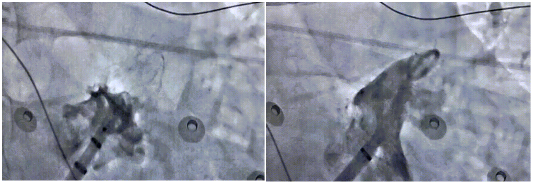

赵育洁教授、孙俊华教授团队手术影像